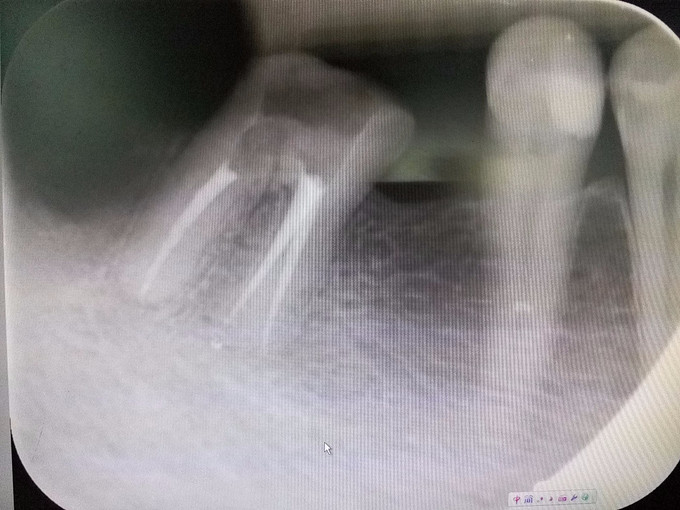

主诉:右下后牙冷热刺激痛两年 现病史:患者自诉两年前右下后牙开始出现冷热刺激痛,无自发痛、夜间痛,无放射到颌面部,今至我科就诊要求治疗 既往史:无特殊,暂未发现药物过敏史

检查:#47 he 面见大量腐质及食物残渣,叩(-),松(-),冷热测迟缓性疼痛,去除刺激后仍持续一段时间,电测有活力,牙龈稍红肿。#47像近中倾斜,#46缺失,#48残根,叩(-),松(-)。

诊断:#47慢性牙髓炎,#48残根 治疗:#47开髓、揭顶,拔髓,冲洗,测量WL,根管预备,封Ca(OH)2两周,ZOE暂封。 两周后复诊去暂封,冲洗根管,测WL,试尖,根充。 拔除#48